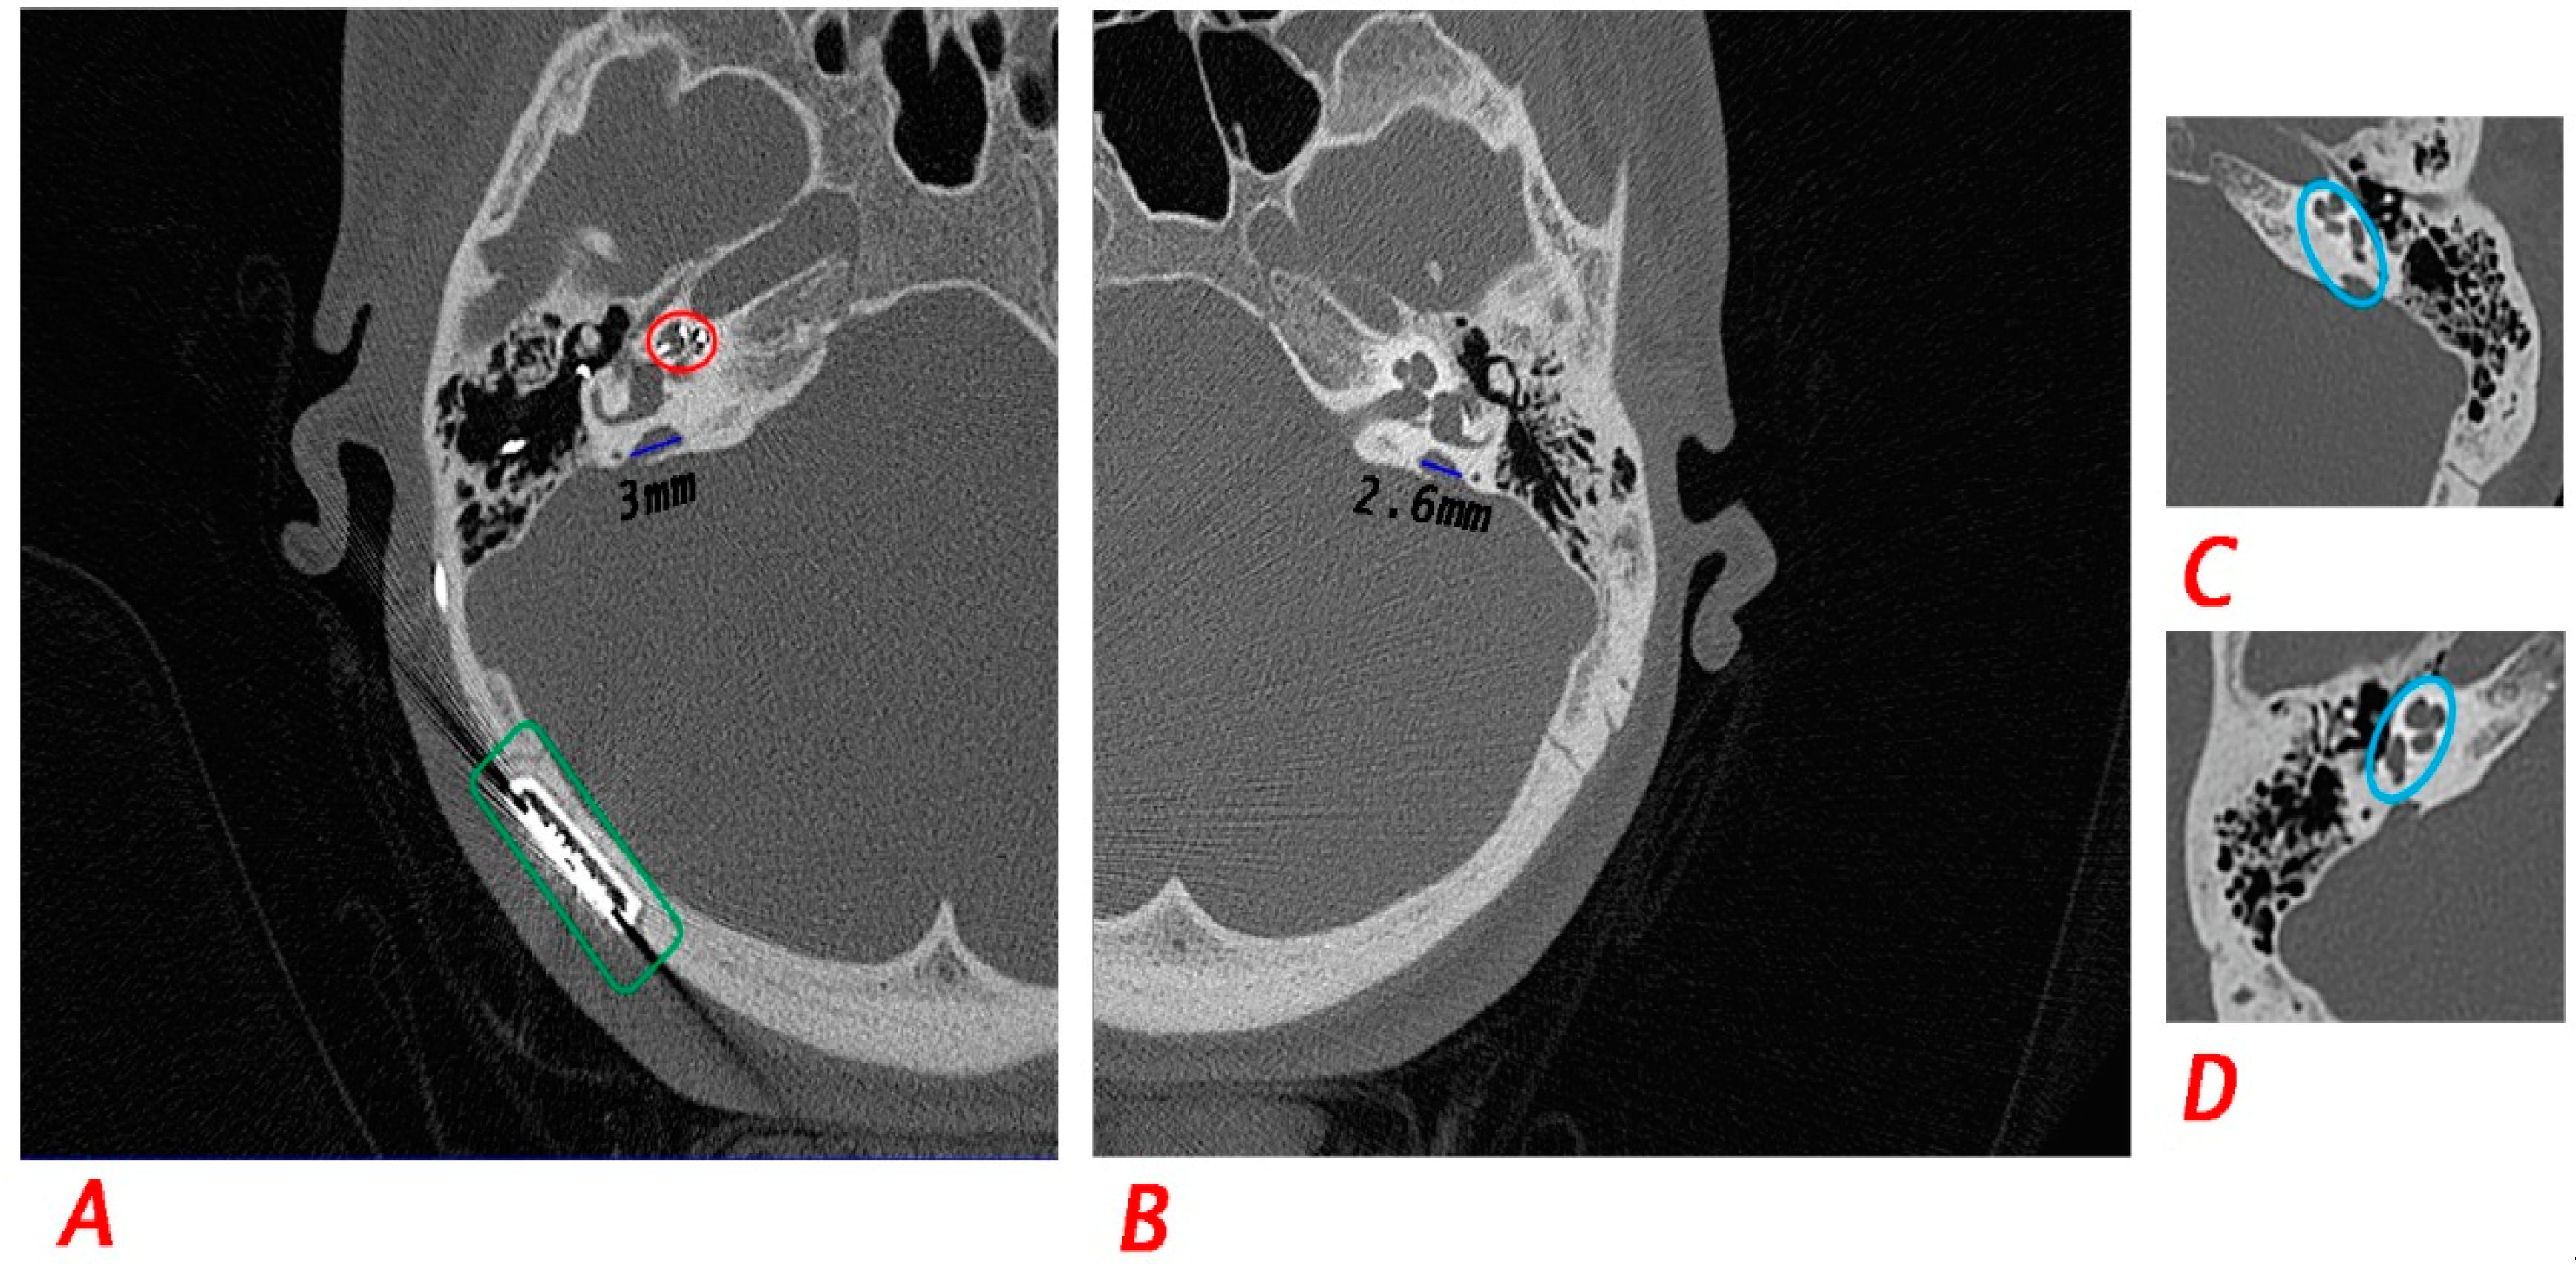

| IV−4 | 17 | F | Congenital | Profound SNHL | Profound SNHL | Yes | Yes | Cochlear implant at 9 years old | Both vestibular aqueducts are dilated (Rt 3 mm, Lt 2.6 mm). | |